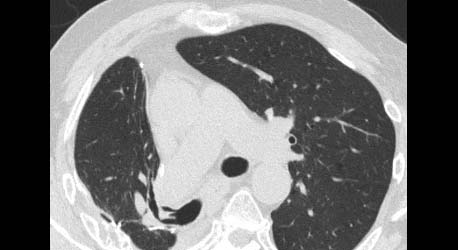

History: a 75 year old man status post partial left upper lobectomy, complicated by pneumothoraces status post chest tube placemente, presented with diffuse crepitus.

A chest radiograph was performed and is shown below. Radiographs: Diffuse subcutaneous emphysema and pneumomediastinum. Patchy basilar opacities In keeping with atelectasis and a probable small amount of left pleural fluid. Small biapical pneumothoraces

Chest CT: Extensive postoperative subcutaneous emphysema and pneumomediastinum. There is a moderate left-sided pneumothorax after left upper partial lobectomy, despite the presence o left chest tube with its lip at the left ape